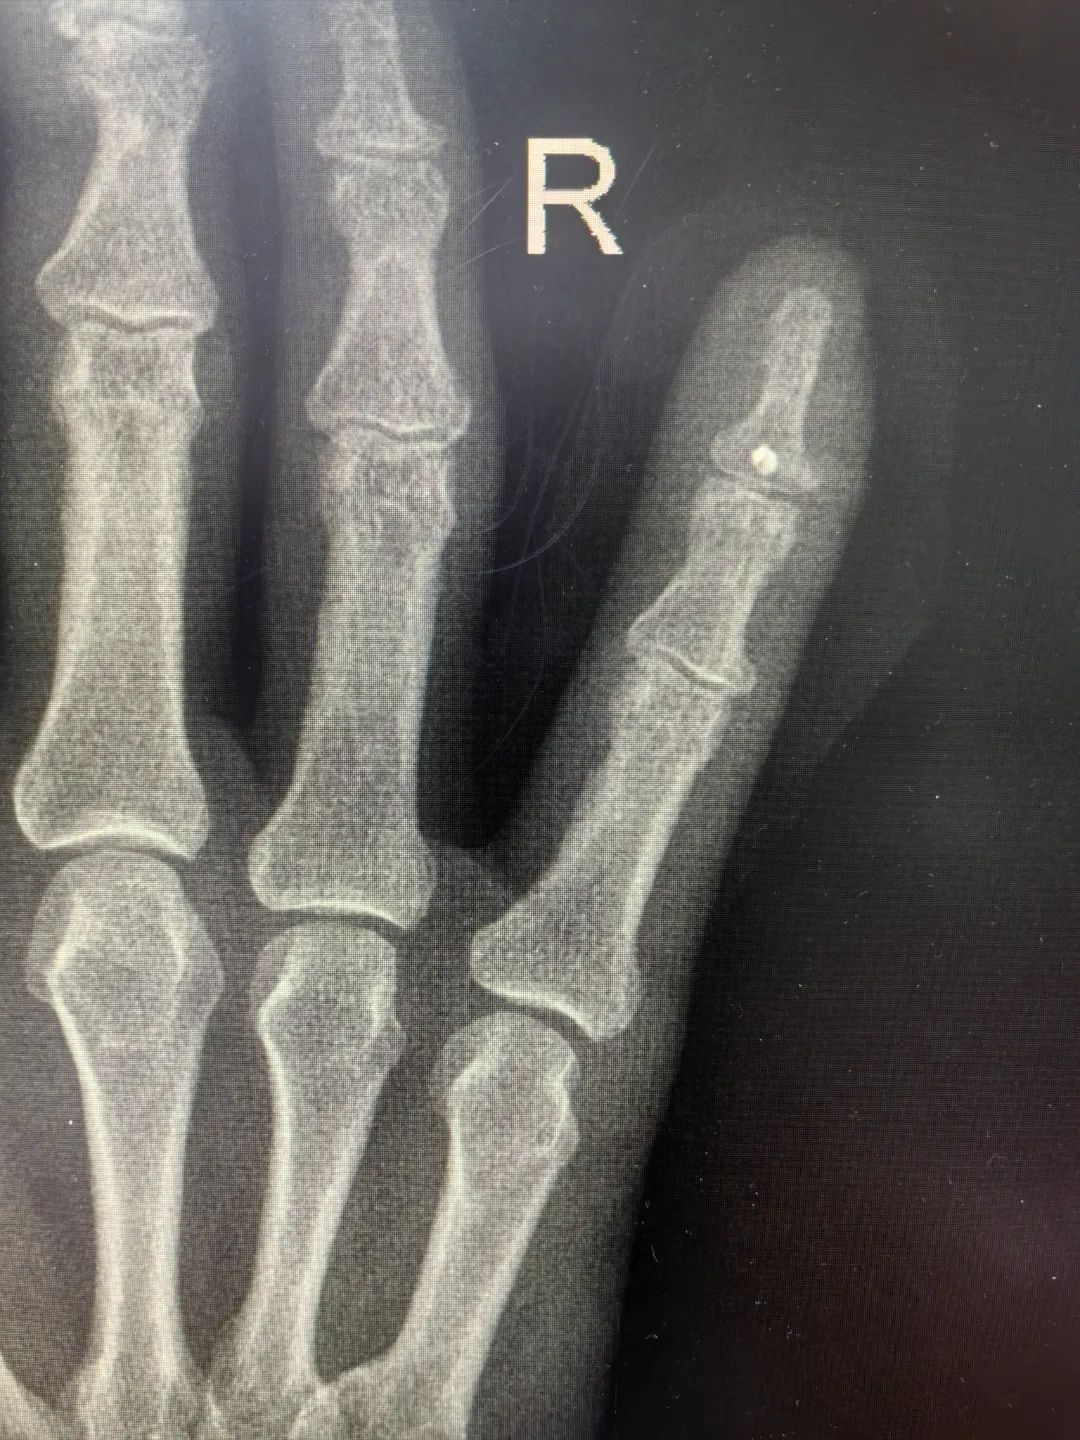

69歲的蔣先生一月前因意外撞擊導(dǎo)致右手小指受傷,當(dāng)時無明顯的皮膚破損但持續(xù)腫脹未愈,近日更是出現(xiàn)受傷手指屈曲無法伸直癥狀。經(jīng)影像學(xué)檢查確診為右小指遠(yuǎn)節(jié)指骨撕脫性骨折,患者慕名求診于我院骨科李強(qiáng)主任。經(jīng)過李主任詳細(xì)查體,明確可通過精細(xì)手術(shù)重建指骨功能。

2月24日入院當(dāng)日,駱州主治醫(yī)師團(tuán)隊(duì)即高效完成術(shù)前評估并實(shí)施微創(chuàng)修復(fù)術(shù)。術(shù)中以2cm微型切口精準(zhǔn)定位,采用錨釘線系統(tǒng)將患者小手指伸肌重新吻合至近端骨性附著點(diǎn),成功實(shí)現(xiàn)骨折解剖復(fù)位。術(shù)后幾天患者即恢復(fù)小指伸展功能,關(guān)節(jié)活動度完全正常。